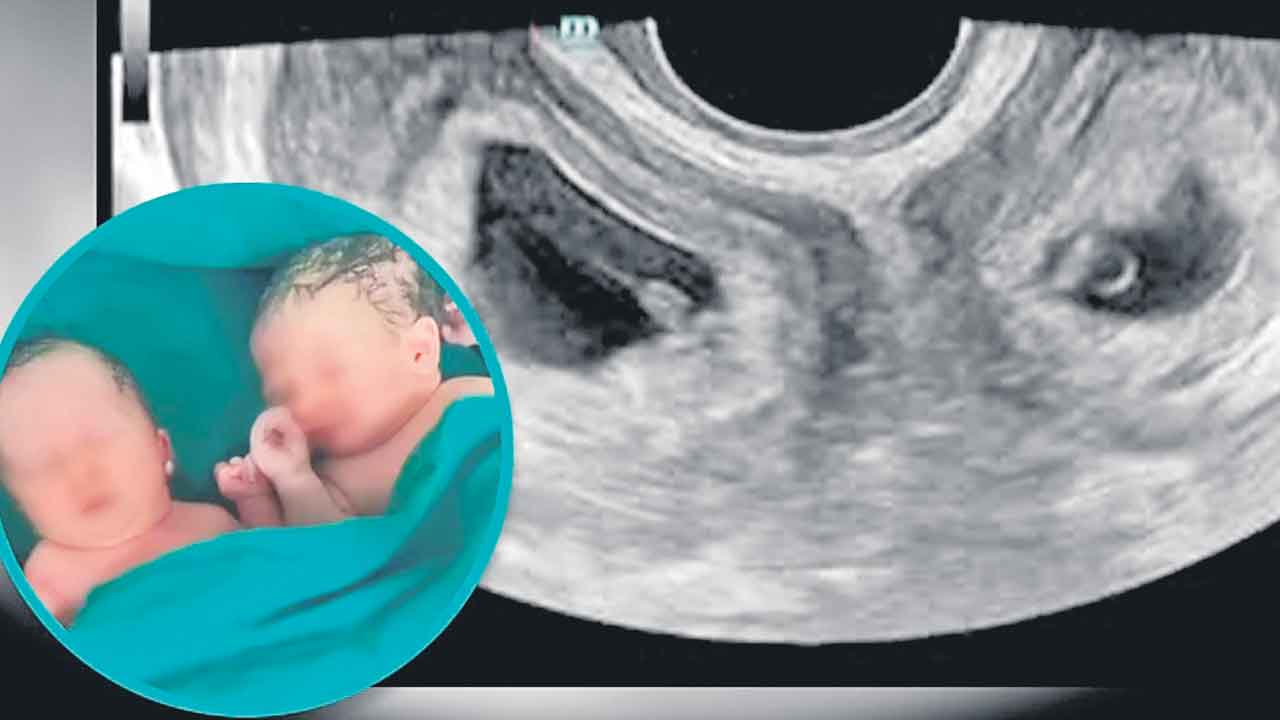

twins | కవల పిల్లల్లో ఒకరు బలంగా, ఇంకొకరు బలహీనంగా ఉండటానికి రకరకాల కారణాలు ఉంటాయి. ముఖ్యంగా వాళ్లు ఒకే అండం నుంచి ఏర్పడ్డారా లేదా రెండు అండాల నుంచి ఏర్పడ్డారా అన్నది ముఖ్యం.